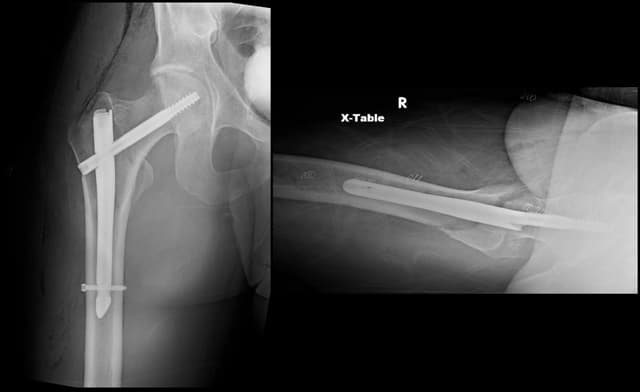

Post-op